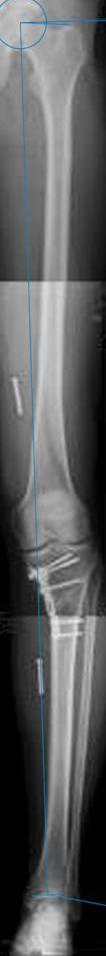

картинки оперированного пациента 40 лет, травма в 2006 году.

оперирован 06.11.2009г - корригирующая остеотомия большеберцовой кости.